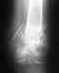

Re: перелом малой берцовой с разрывом синдесмоза

Неободима болт- стяжка с диафизарной накладкой с целью восстановления взаимоотношения в г/стопном суставе